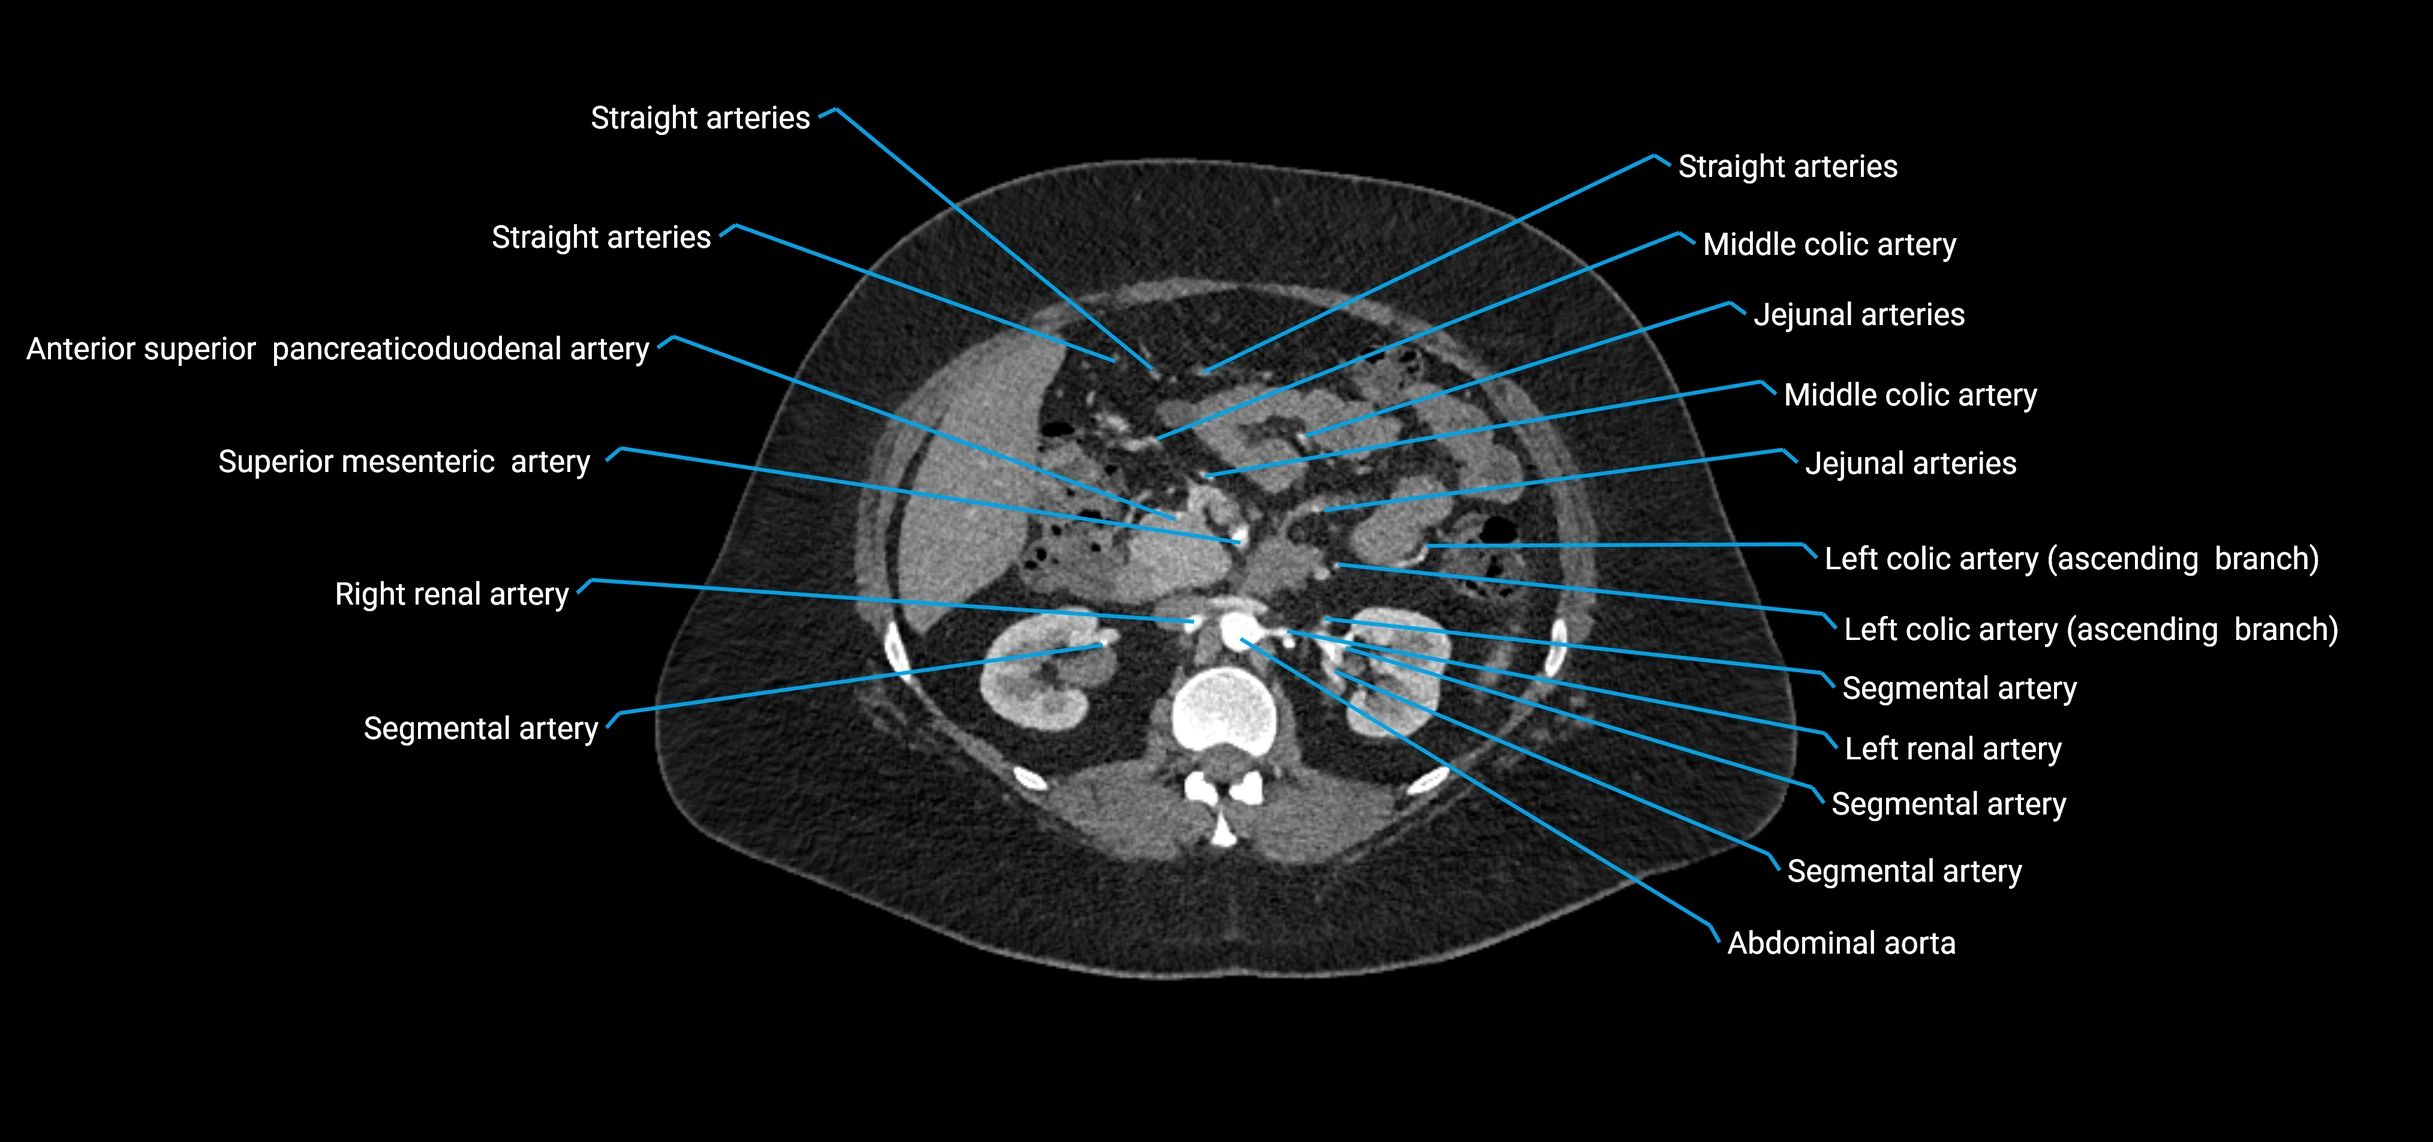

CT images

image

Contrast-enhanced CT (CTA):

• Gold standard for abdominal aortic imaging

• Provides excellent detail of lumen, wall, aneurysm, thrombus, and branch vessels

• Multiplanar and 3D reconstructions help in aneurysm measurement, stent graft planning, and dissection evaluation